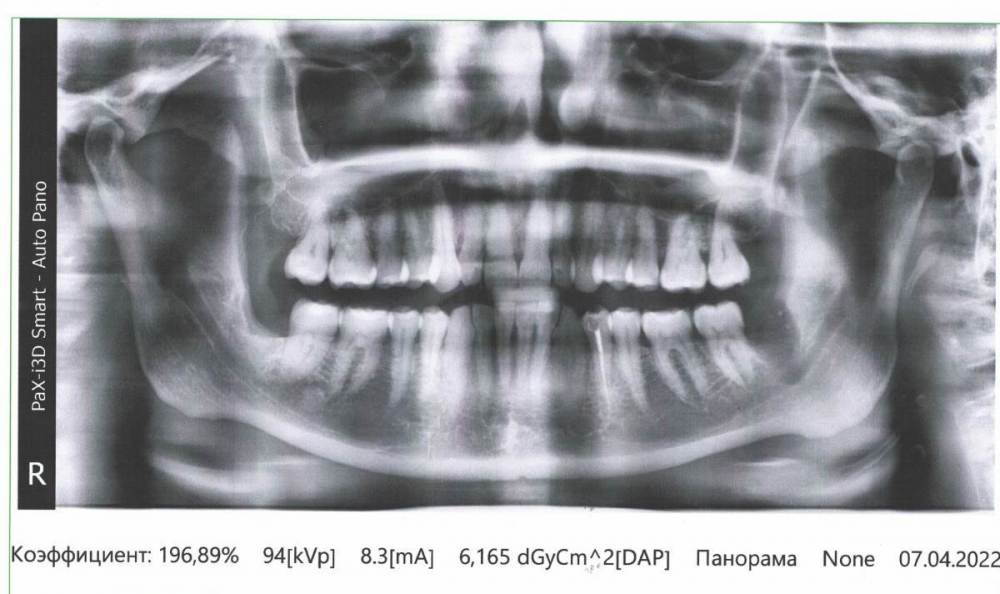

СмирноваД Опубликовано 21 июня, 2022 Поделиться Опубликовано 21 июня, 2022 Здравствуйте Уважаемые стоматологи! Много расписывать не буду, т.к. Долго это. Посмотрите пожалуйста снимок. (также имеется Кт) т.к болит Вся правая сторона головы, и нерв стреляет , то в какой-нибудь верхний зуб, то бывает в нижний какой-нибудь. ТО в язык бывает. Постоянные колики. И отдает по всей стороне головы. От куда это все идет просто не возможно понять. Все это дерганье и напряжение постоянно(щека, верхние зубы, нижние зубы, язык, нос, ухо, висок.).Усиливается к вечеру, но с утра затихает и нарастает в течении полу часа. Стоматологи отправляют к неврологам. Неврологи и стоматоневролог, невралгию отрицают. ЧЛХ тоже особо ни чего страшного не видят. Единственное что видят, это лечить ВНЧС. 1.В июне 2021 года удалили ретинированный 48 зуб. Но боли так и не проходят. Постоянно дергает щеку. Больно глотать слюну и разговаривать. На КТ несколько врачей заметили осколок, но не гарантируют, что после удаления боли пройдут. 2. Имеется еще зуб 1.7. в 2019г. запломбирована коронка и сбоку со стороны щеки тоже пломба прям под десну уходит. Но его не лечили. И он начинает чернеть вокруг пломбы. 3.Так же болит в районе зубов 1.1. и 1.2 при разговоре больно касаться десны и при нажатии возле носа не приятно. Там же пульсирует, нерв стреляет , усиливается при наклоне головы, при физической работе, разговоре. И отдает в нос.. Стоматологи сказали чистить, т.к. много камней было, но это не помогло. 4. И напряжение в 4.1 и 4.2. как буд-то отдает от куда-то. Ссылка на комментарий

СмирноваД Опубликовано 23 марта, 2023 Автор Поделиться Опубликовано 23 марта, 2023 В общем, вскрыл мне зуб 1.2.с периодонтитом. Сделали шину,но как болела вся правая сторона, так и болит. Вечно нерв бьёт, разговаривать и глотать больно, как будто вся сторона воспалена. От шины немного легче. Ещё на КТ видно под 4. 6 зубом какое-то образование, но толком внятного ответа, что это такое, я не услышала. Уважаемые врачи, ответьте пожалуйста на пару вопросов:1.что это такое за белое на снимке и какие последствия от него могут быть. 2.И что думаете про смещение суставного диска кнаружи 5мм(заключение по мрт внчс)?Зарание Спасибо за уделённое время. Ссылка на комментарий

АнтонТЛТ Опубликовано 23 марта, 2023 Поделиться Опубликовано 23 марта, 2023 1) Белое пятно на снимках, скорее всего просто участок более плотной кости (эностоз). Лечения и наблюдения не требует. 2) Выложите заключение по МРТ. Сделайте КТ челюстей с суставами в прикусе (без накусочной пластинки) снимок размером 16*16мм или около того. 1 Ссылка на комментарий